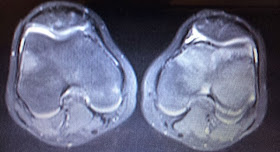

Desgaste y lesiones de cartílago de rodilla...lo que debes saber

Desgaste y lesiones de cartílago de rodilla...lo que

debes saber

Este video lo diseñé para la población general. Es un video largo (21:20), por lo que te pido, te tomes el tiempo.

El tema es el "Desgaste y las Lesiones de Cartílago de la Rodilla". Mi intención es informar a quien sufre de este problema sobre las causas del desgaste de cartílago con enfoque especial en la rodilla, además de revisar toda la gama de opciones de tratamiento que te ayuden a tomar la mejor decisión.